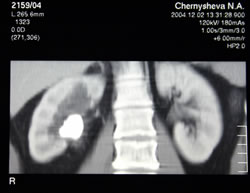

КОМПЬЮТЕРНАЯ

ТОМОГРАФИЯ С БОЛЮСНЫМ КОНТРАСТИРОВАНИЕМ: |

|